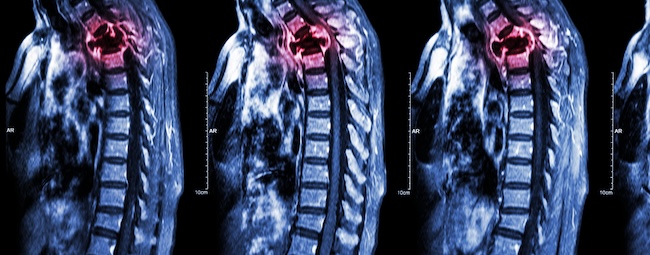

Metastasis vertebrae juga dapat menimbulkan komplikasi lebih lanjut, seperti fraktur kompresi patologis vertebrae (pathologic vertebral compression fractures atau pVCF) dan metastasis kompresi epidural korda spinalis atau metastatic epidural spinal cord compression (MESCC).[1]

Insiden metastasis vertebrae adalah 15,67%. Namun, berdasarkan hasil autopsi, ada sekitar 30% pasien dengan tumor solid ditemukan positif metastasis vertebrae. Hal ini menunjukkan bahwa metastasis vertebrae masih underdiagnosis.[1]

Pemilihan terapi utama pada kasus metastasis vertebrae perlu mempertimbangkan aspek neurologi, onkologi, mekanik, dan sistemik. Modalitas terapi radiasi yang diberi pada pasien metastasis vertebrae bisa berupa external beam radiation therapy (EBRT) konvensional maupun stereotactic body radiation therapy (SBRT).[4]